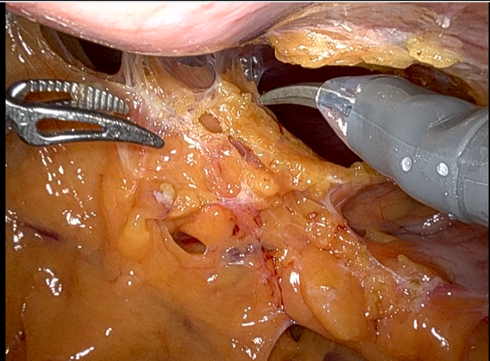

7、 我们采取了“先游离外下侧,掀起肿瘤向内上侧推进”的策略小心游离肿瘤。在肿瘤下极发现供瘤血管,无明显搏动,考虑为静脉,hem-o-lok夹闭后切断。

8、 游离中发现肿瘤背侧、后外侧、上极均有多支腹主动脉发出的血管,分别hem-o-lok结合钛夹结扎、电凝后切断。操作中高度注意保护腹主动脉,游离上极时保护肾动静脉。同时游离时注意不要损伤十二指肠和胰腺,避免患者收到更大创伤,预防并发症。

9、 肿瘤血供丰富,且靠近血管,游离中易出血,轻柔操作,及时止血及助手配合负压吸除积血以保持清晰视野非常重要,助手弯钳辅助暴露。